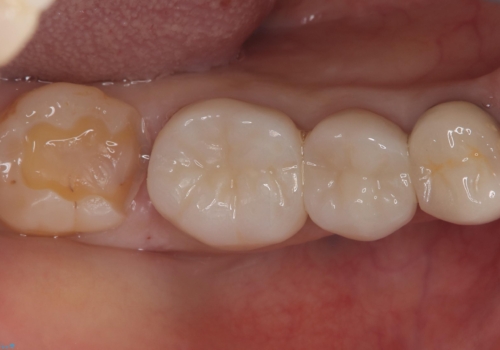

右下7番目の歯に保険適用のメタルインレーが入っており、大きなう蝕などは認めなかったため概形は大きく変えずセラミックインレーへやり替えとなりました。

やり替える過程で古い裏層材やカリエスは全て除去し、新たにCR裏層を行っています。

セラミックインレーセット時はラバーダム防湿を行っています。